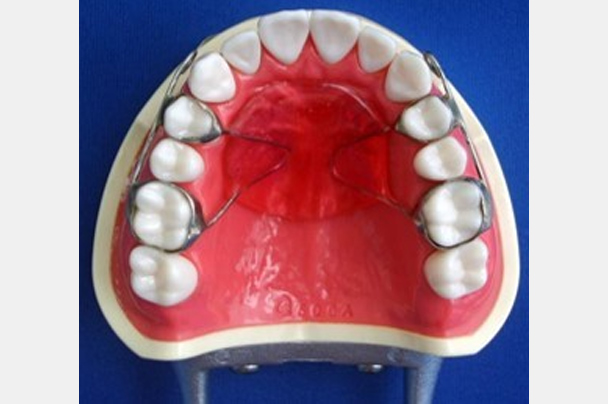

| 治療に用いた装置 | 上顎前方牽引装置(MPA) |

「上顎前方牽引装置」という装置を使用することになりました。この装置は上の歯にセメントで固定する「口腔内装置」と、つけ外し可能な「フェイスマスク」から構成されます。この装置には上あごを前方に成長させる効果があり、骨格的な受け口にアプローチ可能なものです。この装置の有効期間には限りがあり、小学校4~5年生頃にはあまり効かなくなってしまいます。この患者さんは早期に来院してもらえたため効果が期待できると考え、急いで治療を開始しました。フェイスマスクは睡眠時のみ使用しました。フェイスマスクのつけ外しは、最初の数日はお母様に手伝ってもらっていましたが、1か月すれば自分で鏡なしでも着脱できるようになっていました。装置使用による痛みはほとんどなかったとのことです。